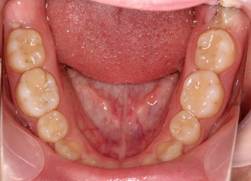

|

治療終了後6年経過時の正面写真

同じく下顎。安定しています。

上顎。保定装置を使用しています。